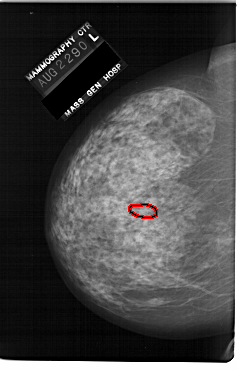

A_1146_1.LEFT_CC

LEFT_CC LINES 6646 PIXELS_PER_LINE 4261 BITS_PER_PIXEL 12 RESOLUTION 43.5 OVERLAY

FILE: A_1146_1.LEFT_CC.OVERLAY

TOTAL_ABNORMALITIES 1

ABNORMALITY 1

LESION_TYPE CALCIFICATION TYPE PLEOMORPHIC DISTRIBUTION LINEAR

ASSESSMENT 4

SUBTLETY 2

PATHOLOGY MALIGNANT

TOTAL_OUTLINES 1

BOUNDARY